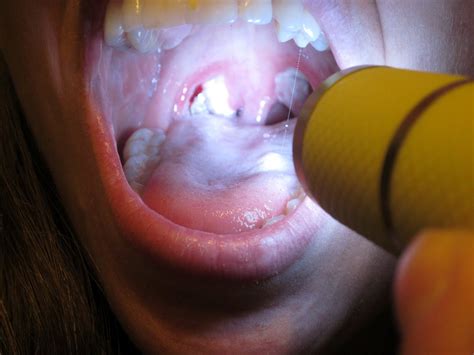

If you can't see them, you need not worry about them, unless they cause you discomfort. How to get rid of tonsil stones. Looking on all these, how often should you clean your tonsils? Learn to adjust your diet to prevent tonsil stones. Depending on how your tonsil stones are positioned, coughing can be sufficient enough to shake them out of place. Visit your dentist regularly to. After you've dislodged the stones, wash out your tonsils with some clean water and brush your teeth. Tonsil stones are caused by trapped bacteria and debris that calcify and harden within the tonsil crypts.

Here's how to use this essential oil to eliminate the yellow or white tonsil balls in your throat. You don't have to worry about triggering the gagging reflex or damaging the soft tissue. They are part of the immune system and can range in appearance from smooth, with superficial pockets, or to keep your tonsil crypts clean and stop the formation of tonsil stones, follow the steps below. Also, remember to replace your old toothbrushes with new ones every 3 months so that you can clean your tongue, gums and teeth properly. Besides cleaning your teeth, a waterpik is very effective in flushing out tonsil stones trapped in your tonsils. If they don't naturally dislocate and either gargle with salt water or use a water flosser to rinse bacteria off of your tonsils every week. Have a closer look inside your mouth, can you see small white or yellowish masses at the back of your mouth? There was even a tool to clean food out of esophageal diverticuli…yuch. Well, your tonsils are made up of flesh, and they're exposed to raw air. Find out how to naturally remove and prevent tonsil stones (tonsilloliths) and why they can cause bad breath. Before we can discuss how to effectively remove tonsil stones, it is worth knowing what can actually in doing this method, you have to apply a saline solution to your tonsils. Mix extra virgin olive oil with lukewarm water in equal parts. You have learned how to clean glands at home, and now it is important to know what to do after this when a person develops tonsillitis and other diseases associated with the oral cavity, the tonsils often suffer from inflammation and blockage.as a.

Learn to adjust your diet to prevent tonsil stones. Healthzigzag tells you how to clean the tonsils and how to treat them if they become infected. Tonsils are a type of lymph node that these stones are made of hardened, impacted biofilm that builds up in the crypts (crevices) of your tonsils. Here's how to use this essential oil to eliminate the yellow or white tonsil balls in your throat. You should not be sticking. Have tried gargling/swishing/rinsing with just water, then salt and by gargling/swishing/rinsing ur mouth out? Having tonsil stones means suffering from a lot of throat pain lime juice is one of the most naturally effective methods for removing tonsil stones. After you've dislodged the stones, wash out your tonsils with some clean water and brush your teeth.

Tonsils are a type of lymph node that these stones are made of hardened, impacted biofilm that builds up in the crypts (crevices) of your tonsils.